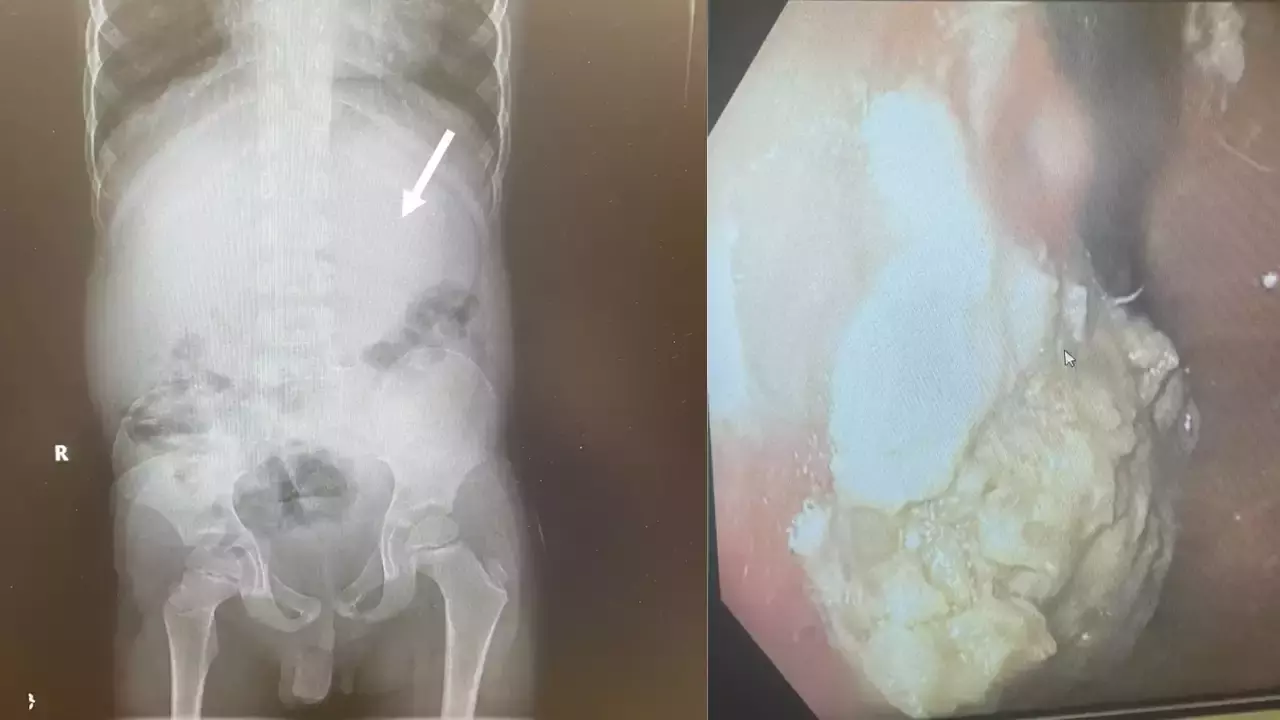

ക്ലീവ്ലാൻഡ് ക്ലിനിക്കിലെ ഡോ. ചിസൈറ്റ് ഇഹിയോനുനെക്വുവിന്റെ നേതൃത്വത്തിലുള്ള സംഘമാണ് ശസ്ത്രക്രിയ നടത്തിയത്